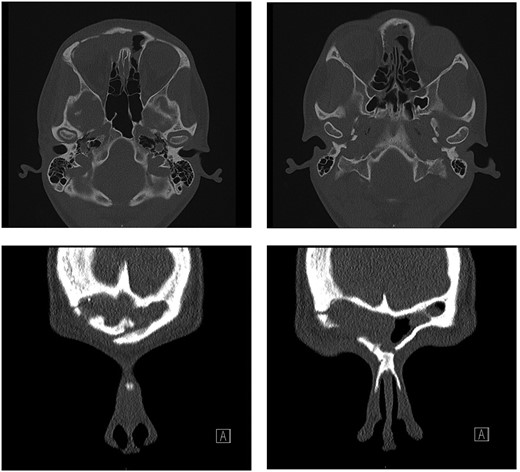

Post-operatively, the patient recovered well with no complications. Examination of the eye four weeks after surgery showed significant improvement—visual acuity was 6/6 on the right, 6/5 on the left. The visual acuity improved to 6/6 on both sides 10 months after surgery; however, there was a residual hypotropia. A repeat CT scan at 4 months post-surgery displayed no bulky residual disease and improvement of proptosis (Fig. 3).

Repeat CT scan at 4 months after surgery, demonstrating no residual disease and radiological improvement of proptosis.